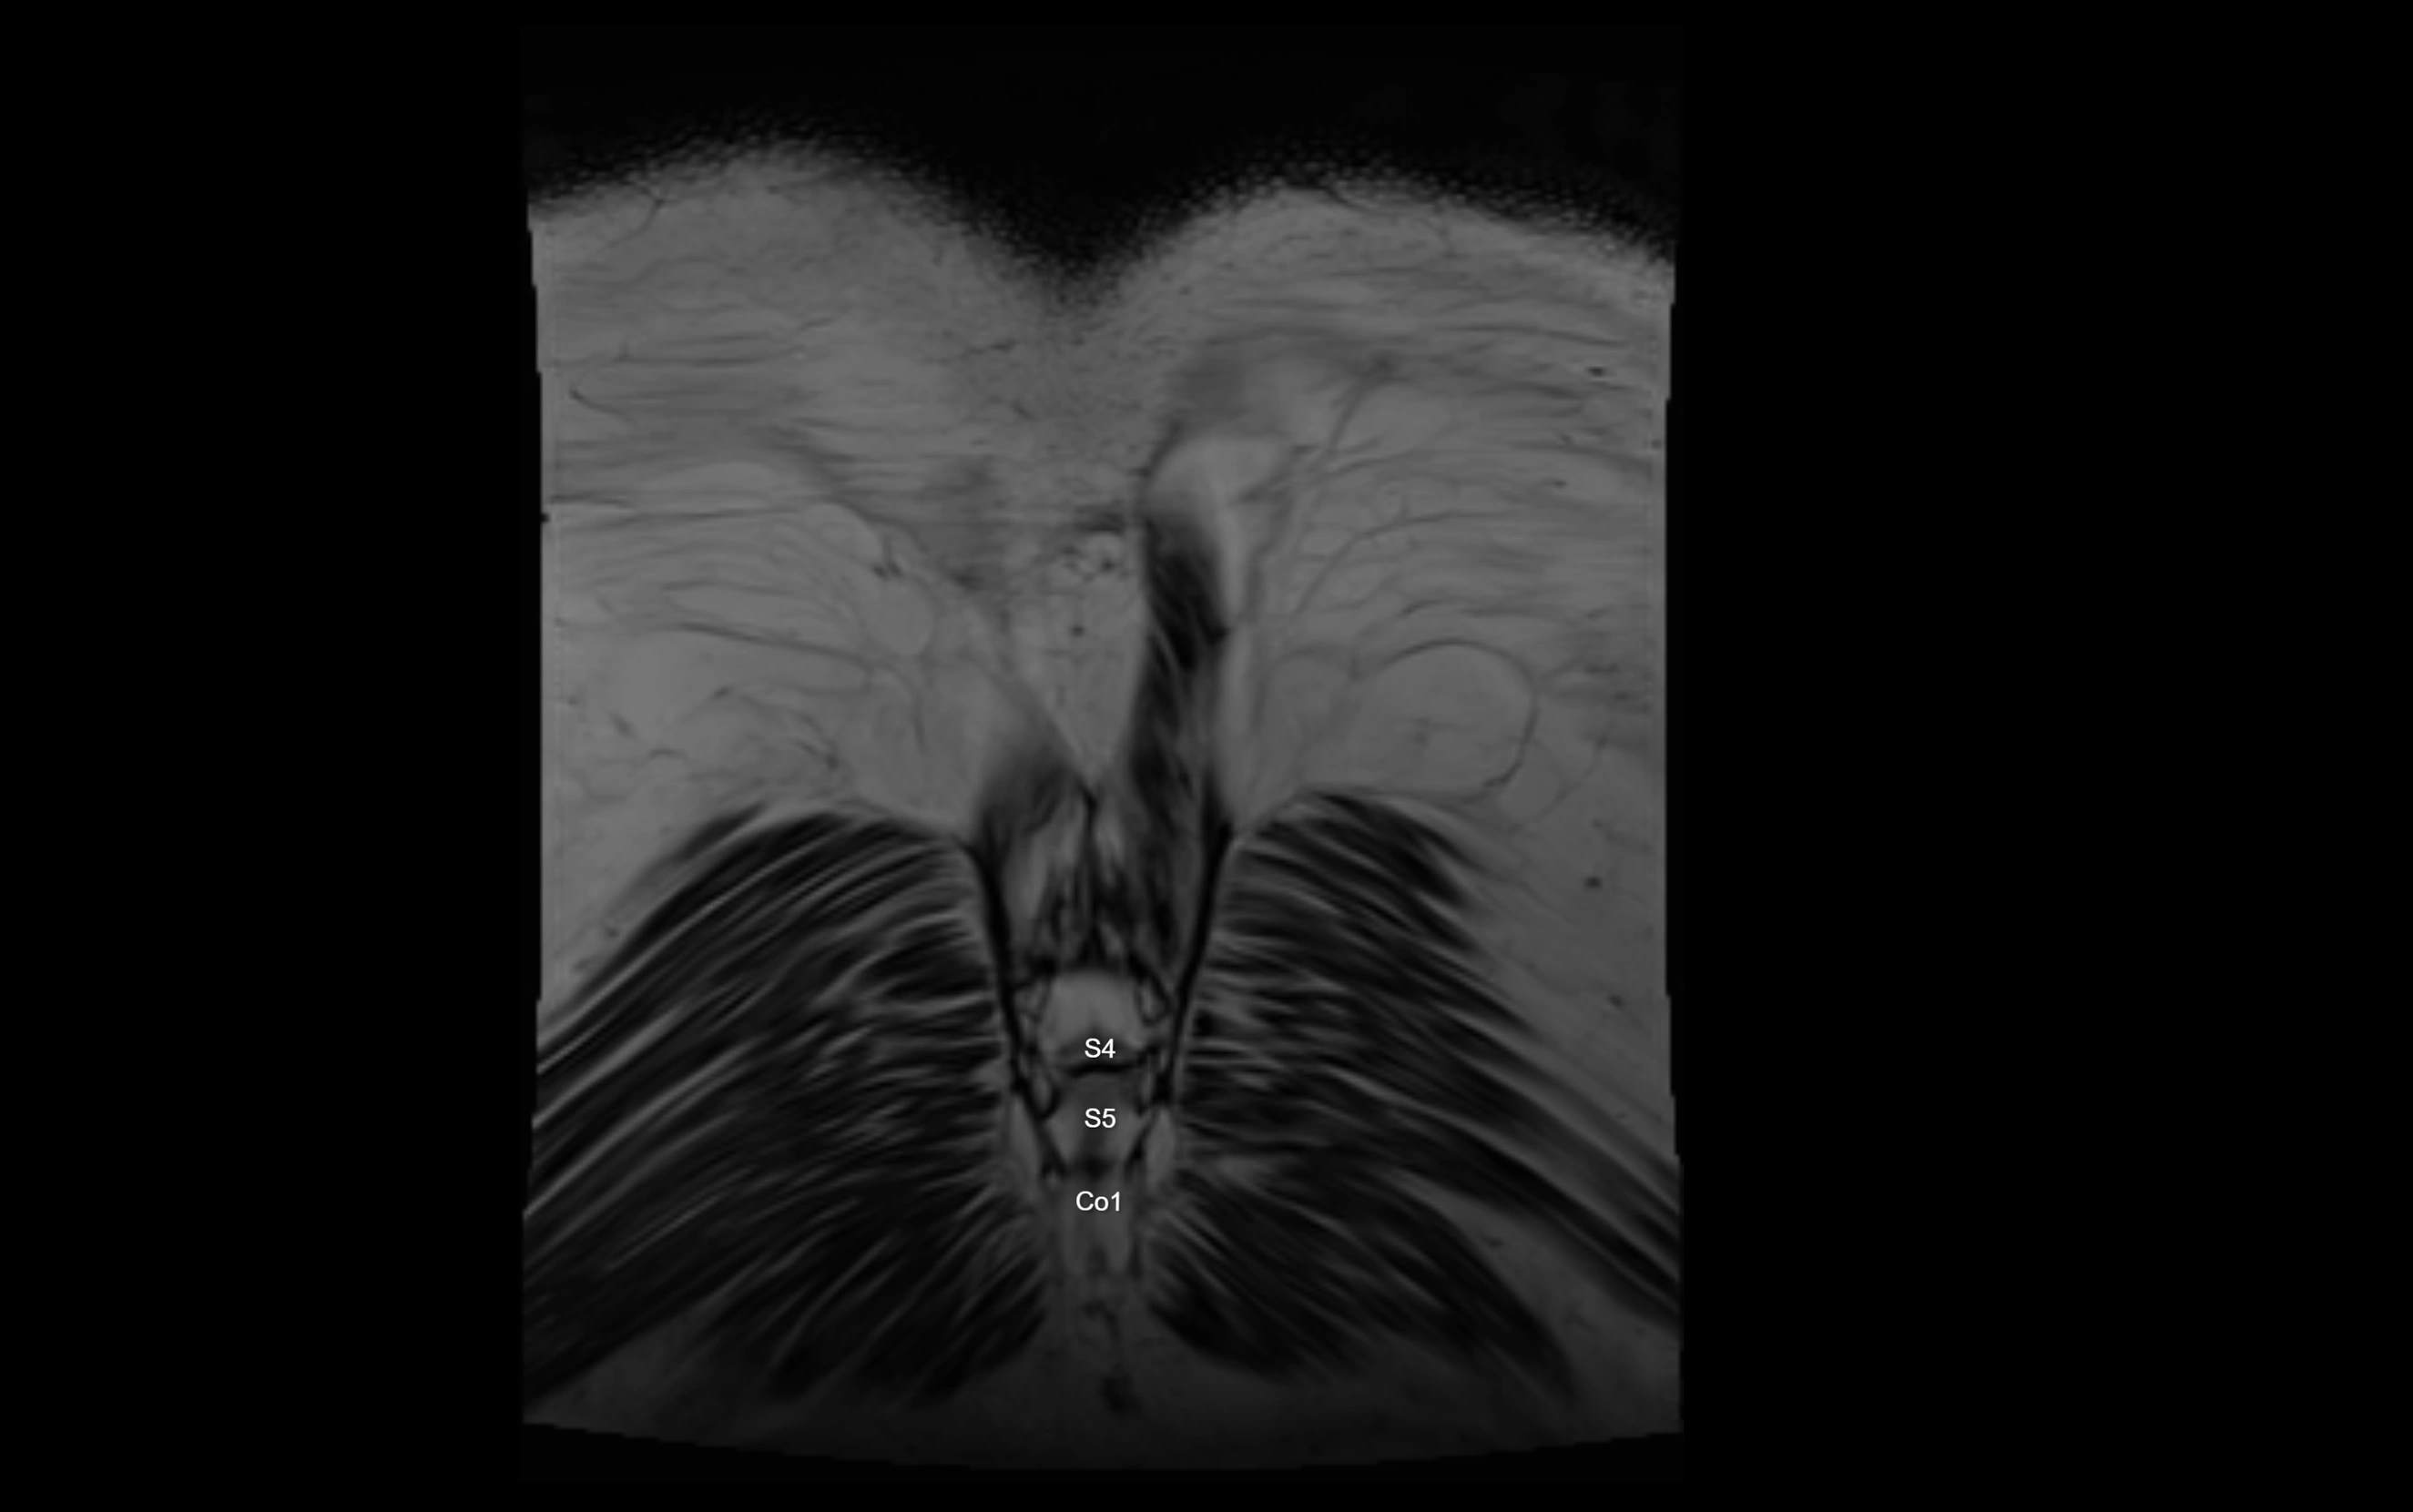

The anococcygeal nerve is a small sensory nerve derived from the coccygeal plexus, which itself is formed by the ventral rami of S4, S5, and the coccygeal nerve (Co1). Although tiny, this nerve plays an important role in supplying the skin of the coccyx and the area between the anus and coccyx. It passes through the sacrotuberous ligament and runs in the midline behind the coccyx.

• Arises from the coccygeal plexus, formed by ventral rami of S4, S5, and Co1

MRI image

image